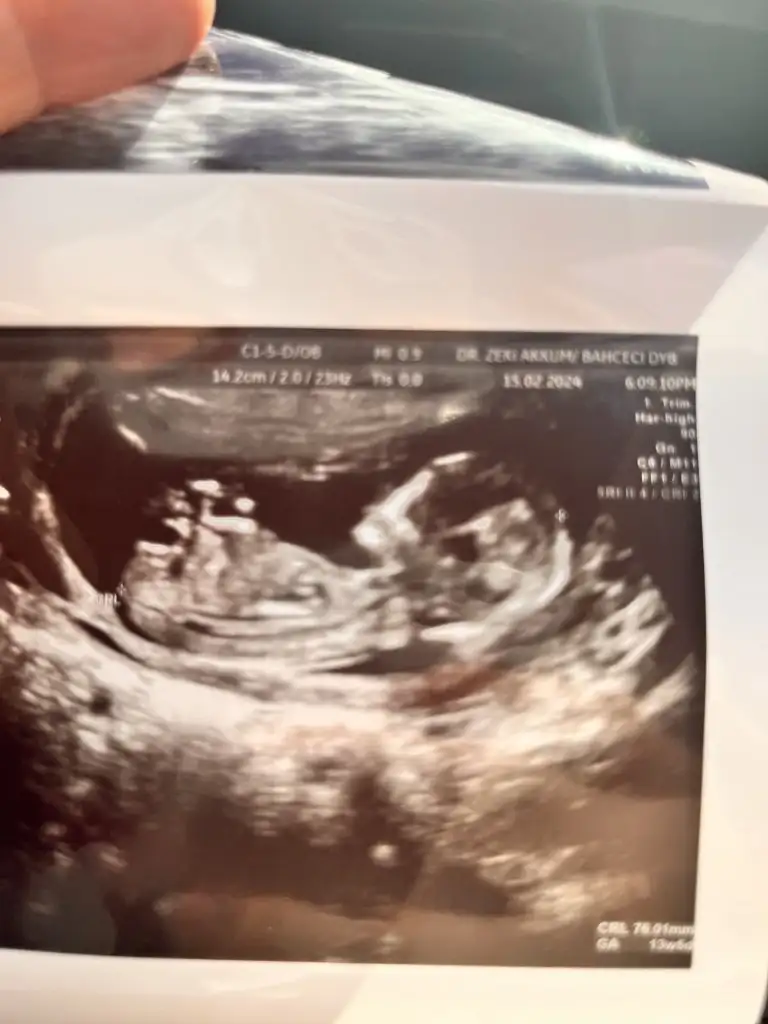

Kızlar bugün kontrolüm vardı şuan 12.haftamın içindeyim 2 li tarama yapıldı ama cinsiyetine erken olduğu için doktor bir şey demedi. Bir ay sonraya çağırdı gerçekten merak ediyorum tecrübeli olanlar varsa tahmin edebilir miBi de 2 gün geç döllenme olmuştu başta ama şuan 1 gün önden gidiyormuş belki işinize bana da yorum yaparmisiniz bende çok merak ediyorum

Bana da yorum yaparmisiniz bende çok merak ediyorumKızlar bugün kontrolüm vardı şuan 12.haftamın içindeyim 2 li tarama yapıldı ama cinsiyetine erken olduğu için doktor bir şey demedi. Bir ay sonraya çağırdı gerçekten merak ediyorum tecrübeli olanlar varsa tahmin edebilir miBi de 2 gün geç döllenme olmuştu başta ama şuan 1 gün önden gidiyormuş belki işinize yarar

Yerleşim yeri erkek ama kemik yapısı kız. Bence minnoş bir kız olacak6-7 haftalık usg görüntüsü varsa ona da yorum yapayım